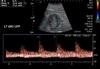

Q

Name 2 radiotraces and what they are used for in urology

2) Tubular concentration phase

-Lasts 1-5 minutes